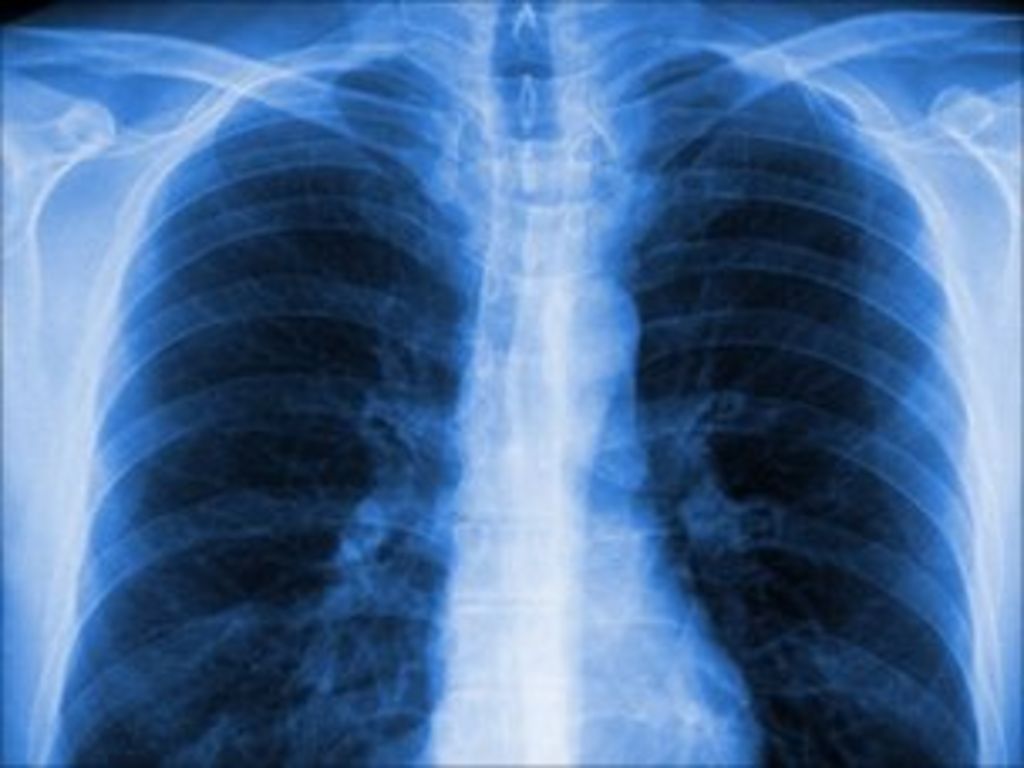

Blood Clot At Lung Level, At The Left Lower Lobe. X Ray, Frontal View Blood Clots Lungs It can happen when a blood. a pulmonary embolism (pe) is a blood clot in your lung that creates a blockage. learn about the recovery time, hospital stays, medication, and tips for people with pulmonary embolism. blood clots in lungs: This causes issues with blood flow and oxygen levels in your lungs. a pulmonary embolism, or. Blood Clots Lungs.